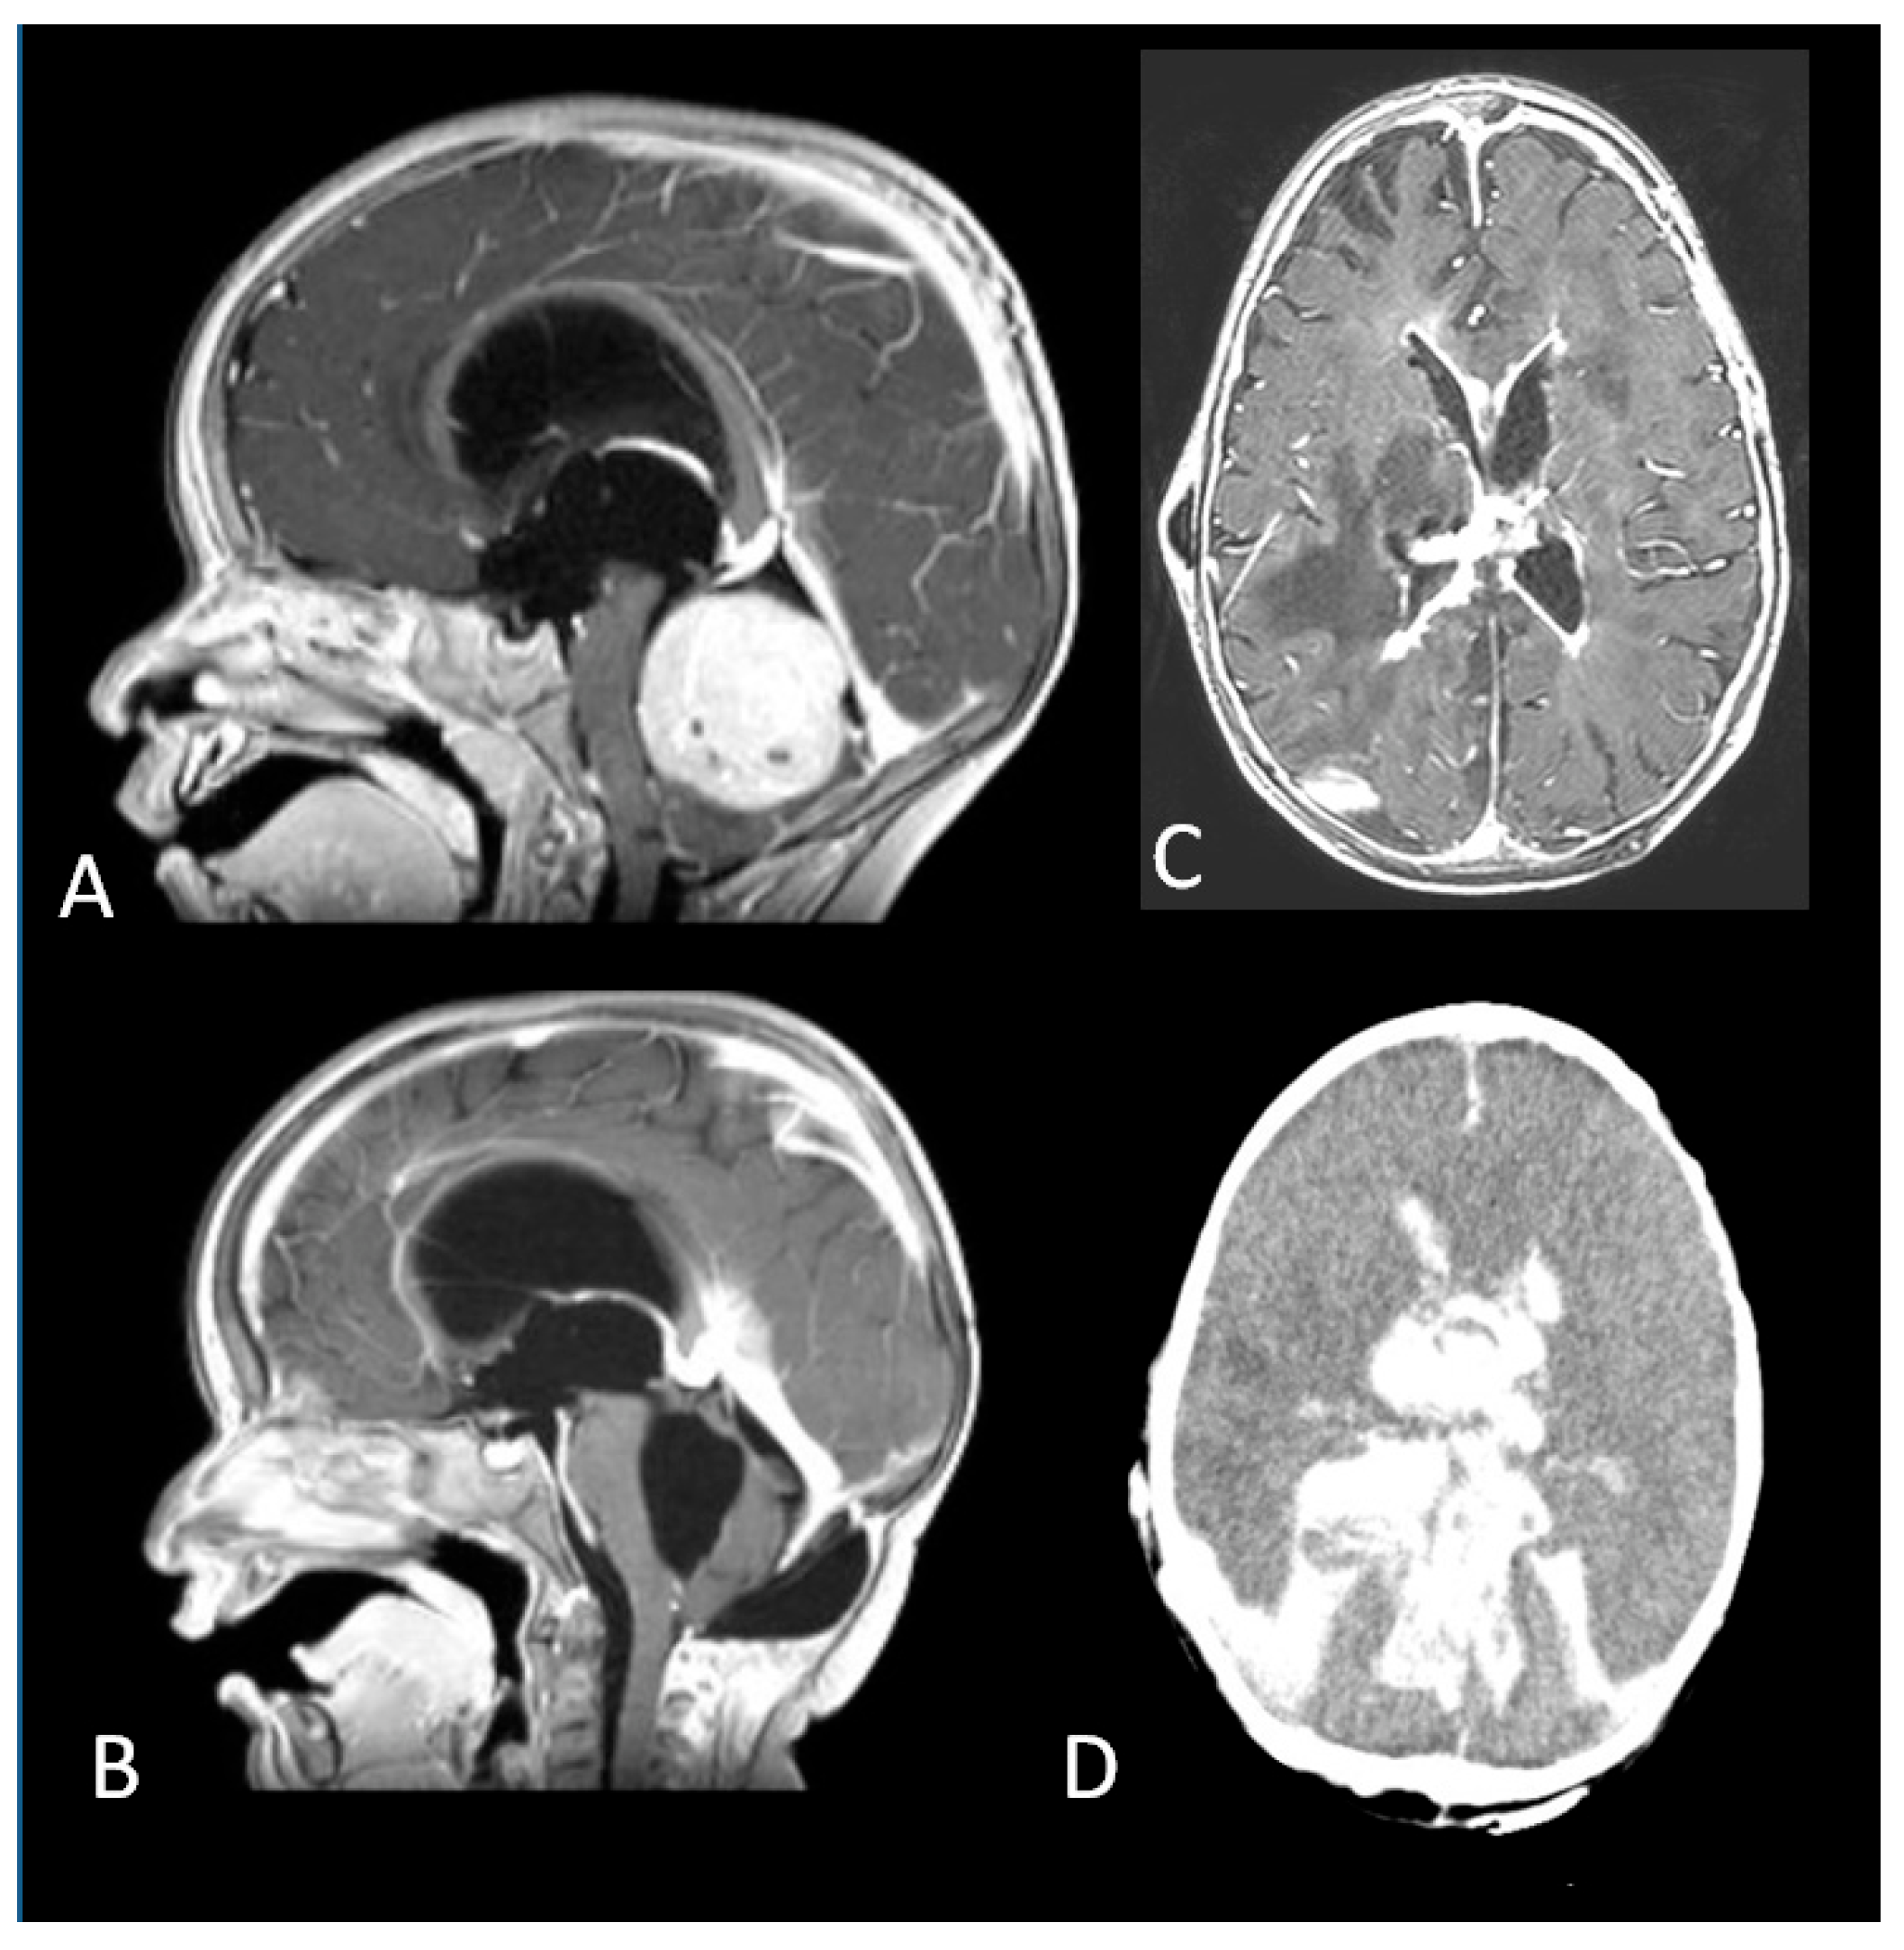

Seven patients had a diagnosis of medulloblastoma, namely large cell medulloblastoma in one case and desmoplastic/nodular pathology in six cases, with cranial metastases in two. The former underwent a biopsy and died of gastro-intestinal haemorrhage due to acute chemotherapy toxicity two months later. The other patients had surgery (one partial removal and five GTR) and induction chemotherapy followed by high dose myeloablative chemotherapy with autologous stem cell rescue (HDC/ASCR). Two of them died of complications several months after treatment: one patient developed chronic renal and cardiac failure associated with myelodysplasia, resulting in hemocoagulative disorders. She also experienced multiple episodes of shunt failure and a mycotic ventriculitis and eventually died of massive intraventricular haemorrhage (Figure 5).

Figure 5.

(A). A fourth ventricular tumour arising from the cerebellar vermis. (B). Complete Resection of a desmoplastic medulloblastoma. (C). Mycotic ventriculitis (D). Intraventricular haemorrhage.

The second patient experienced cardiac failure and died when she was on mechanical circulatory support as a bridge to a heart transplant.

One child died of acute toxicity three months after diagnosis due to acute renal failure following the second cycle of chemotherapy.